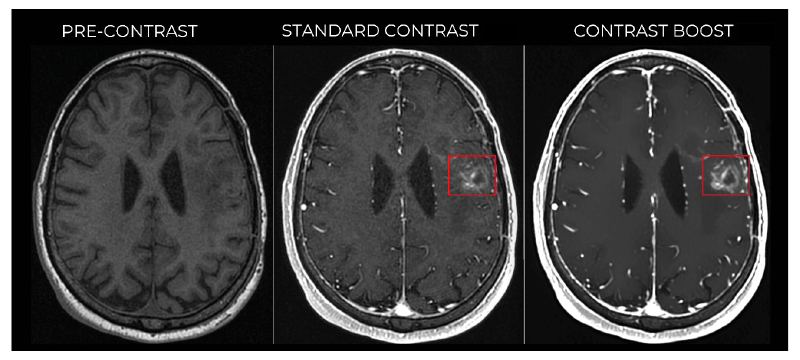

Quantitative analysis demonstrates that the DL-based contrast boosting algorithm significantly enhances lesion conspicuity and image quality when used in combination with gadopiclenol at a reduced dose. The observed increase in contrast enhancement suggests that CB images obtained with 0.05 mmol/kg gadopiclenol are quantitatively comparable to a doubled contrast dose (Figure 1). These findings support the synergistic use of high-relaxivity contrast agents and DL-based contrast boosting as a strategy for gadolinium dose reduction while maintaining or improving diagnostic performance.

Figure 1: Representative axial T1‑weighted brain MRI showing pre‑contrast (left), standard post‑contrast

The enhancing lesion (red square) is more clearly visualised on contrast‑boosted images, with improved conspicuity and delineation compared with standard post‑contrast imaging.